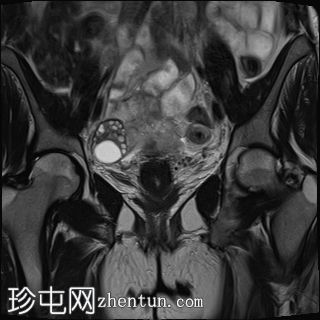

脂肪抑制像

冠状位

左侧卵巢增大、水肿,位置异常,卵泡呈周边排列

左侧卵巢血管扭转,呈漩涡征

左侧卵巢实质出血性改变

可见左侧卵巢少量囊肿,内含血信号

未见明显强化软组织肿块

上述左侧卵巢增大、水肿、位置异常、卵泡呈周边排列、实质出血的特征提示卵巢扭转伴出血。梗死。

患者被转诊至妇科医生处,并紧急行输卵管卵巢切除术。病理检查显示广泛的出血性梗死,卵巢包膜下仅残留薄薄一层完整组织。未发现恶性肿瘤